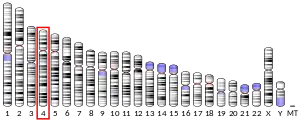

Alpha-synuclein (aSyn) is a protein that, in humans, is encoded by the SNCA gene.[5] Alpha-synuclein is a neuronal protein that regulates synaptic vesicle trafficking and subsequent neurotransmitter release.[6][7]

Familial Parkinson's disease is associated with mutations in the -synuclein (SNCA) gene. In the process of seeded nucleation, alpha-synuclein acquires a cross-sheet structure similar to other amyloids.[12]

In rare cases of familial forms of Parkinson's disease, there is a mutation in the gene coding for alpha-synuclein. Five point mutations have been identified thus far: A53T,[110] A30P,[111] E46K,[112] H50Q,[113] and G51D;[114] however, in total, nineteen mutations in the SNCA gene have been associated with parkinsonism: A18T, A29S, A53E, A53V, E57A, V15A, T72M, L8I, V15D, M127I, P117S, M5T, G93A, E83Q, and A30G.[115]

It has been reported that some mutations influence the initiation and amplification steps of the aggregation process.[116][117] Genomic duplication and triplication of the gene appear to be a rare cause of Parkinson's disease in other lineages, although more common than point mutations.[118][119] Hence certain mutations of alpha-synuclein may cause it to form amyloid-like fibrils that contribute to Parkinson's disease. Over-expression of human wild-type or A53T-mutant alpha-synuclein in primates drives deposition of alpha-synuclein in the ventral midbrain, degeneration of the dopaminergic system and impaired motor performance.[120]